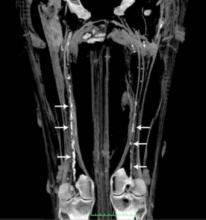

Abbott announced positive long-term results for the company's innovative Absorb Bioresorbable Vascular Scaffold (BVS). Three-year results from 101 patients in the second stage of the ABSORB trial were presented at the 62nd Annual Scientific Session of the American College of Cardiology (ACC) in San Francisco. Absorb is commercially available in Europe as well as other international markets and is an investigational device in the United States.